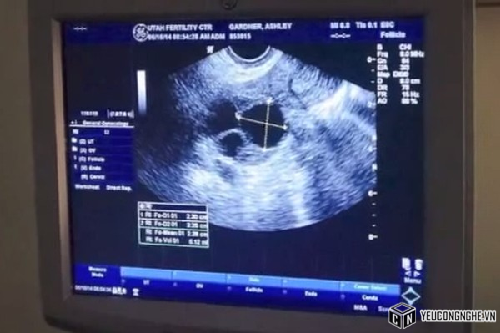

Hình ảnh siêu âm thai của cô Ashley